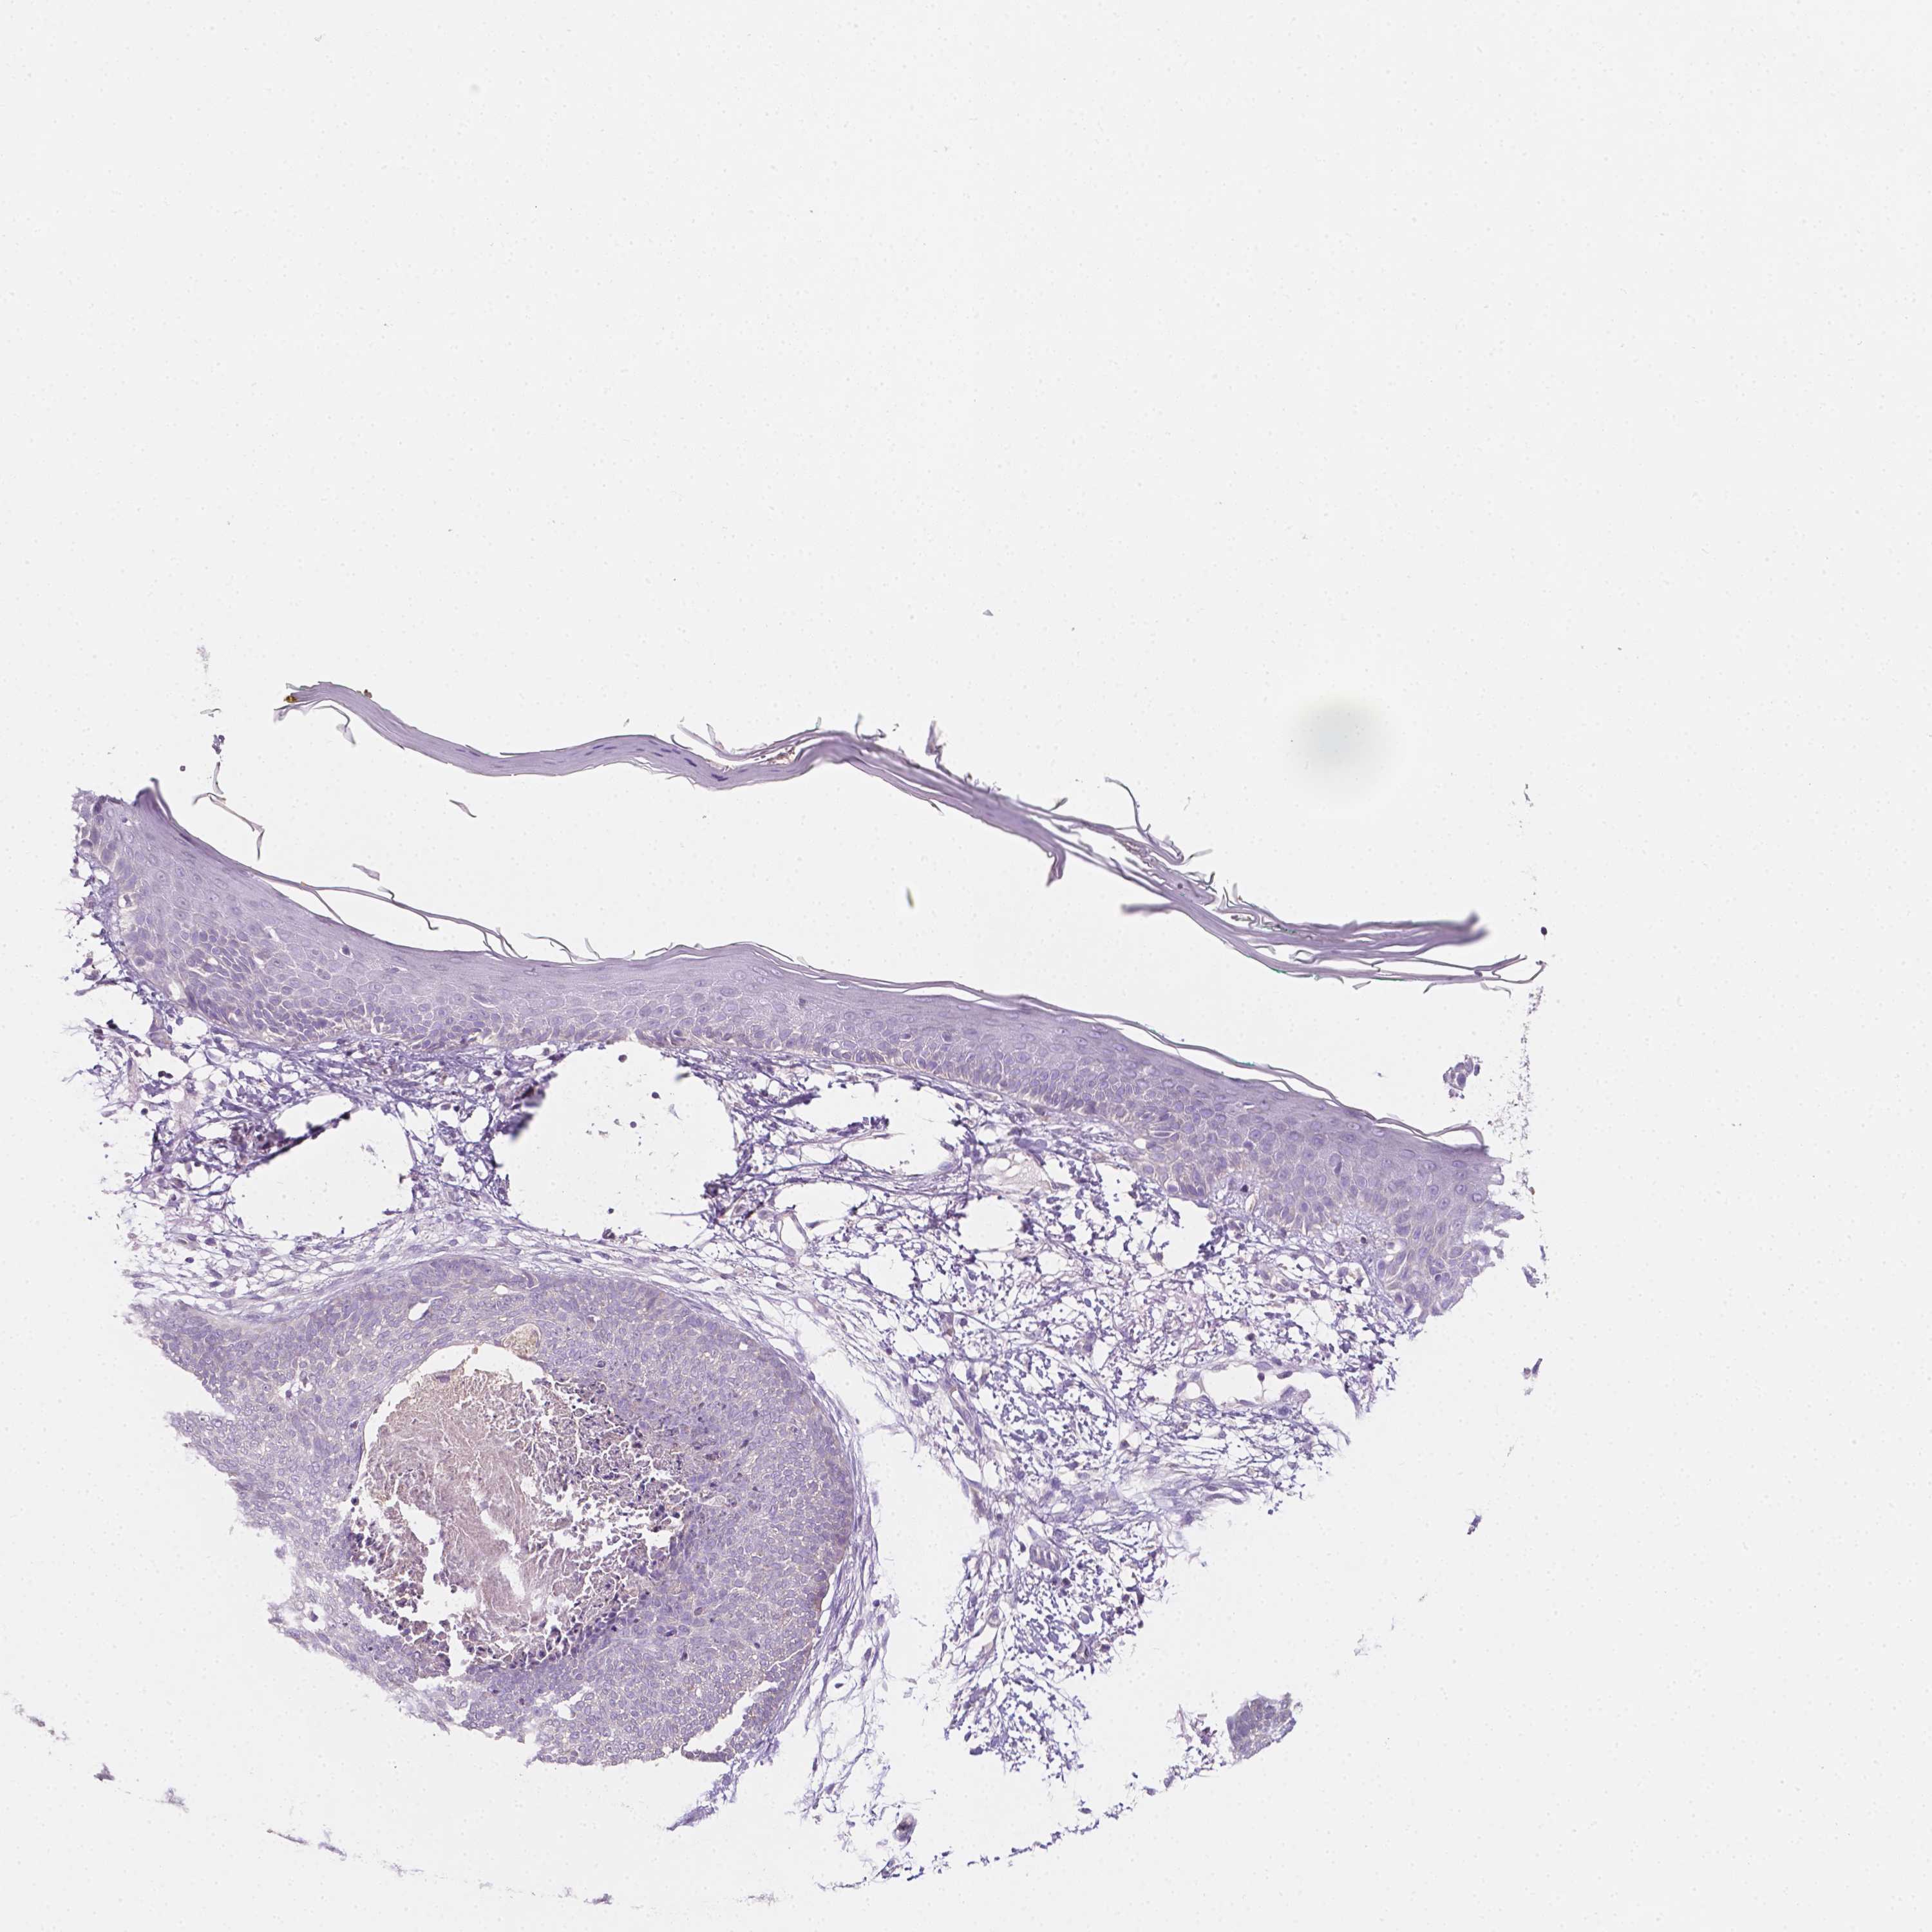

SKIN CANCER - Protein expressioni

A mouse-over function shows sample information and annotation data. Click on an image to view it in a full screen mode. Samples can be filtered based on level of antibody staining by selecting one or several of the following categories: high, medium, low and not detected. The assay and annotation is described here.

Each image is clickable and will lead to virtual microscopy that enables deeper exploration of all samples and also displays staining intensity scores, fraction scores and subcellular localization as well as patient and tissue information for each sample.

Staining

High

Medium

Low

Not detected

Intensity

Strong

Moderate

Weak

Negative

Quantity

>75%

75%-25%

<25%

None

Location

Nuclear

Cytoplasmic/membranous

Cytoplasmic/membranous,nuclear

Basal cell carcinoma

Squamous cell carcinoma in situ, NOS